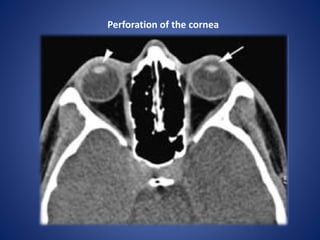

Perforation of the cornea

• #13 Perforation of the cornea. Axial CT scan shows perforation of the cornea with hypotony of the aqueous chamber. The fluid space between the cornea and the lens on the right side (arrowhead) is diminished compared to the left. A normal aqueous chamber is seen on the left side (arrow).